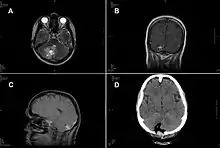

A case of intracranial T. crassiceps tapeworm cysticercosis with severe involvement of the cerebellum is described. A 51-year-old German woman was hospitalized because of progressive headache, nausea, and vomiting. The signs and symptoms had started 2 weeks before, and intensity had been increasing ever since. At the time of admission, the patient showed cerebellar ataxia but no further neurologic deficits. She did not have fever or other symptoms. She had no known chronic preconditions or recent hospital stays and had never taken immunosuppressant drugs. She had no family history of neurologic symptoms or malignant diseases. Combined surgical removal of the larvae and treatment with albendazole and praziquantel led to a complete cure in this nonimmunocompromised patient. The organism was unequivocally identified by molecular methods, thus avoiding a misdiagnosis of Taenia solium tapeworm cysticercosis.[5]